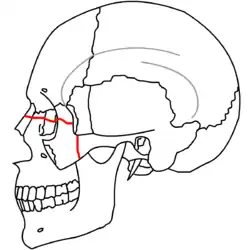

At the beginning of the 20th century, René Le Fort mapped typical locations for facial fractures; these are now known as Le Fort I, II, and III fractures (right).[7] Le Fort I fractures, also called Guérin or horizontal maxillary fractures,[14] involve the maxilla, separating it from the palate.[15] Le Fort II fractures, also called pyramidal fractures of the maxilla,[16] cross the nasal bones and the orbital rim.[15] Le Fort III fractures, also called craniofacial disjunction and transverse facial fractures,[17] cross the front of the maxilla and involve the lacrimal bone, the lamina papyracea, and the orbital floor, and often involve the ethmoid bone,[15] are the most serious.[18] Le Fort fractures, which account for 10–20% of facial fractures, are often associated with other serious injuries.[15] Le Fort made his classifications based on work with cadaver skulls, and the classification system has been criticized as imprecise and simplistic since most midface fractures involve a combination of Le Fort fractures.[15] Although most facial fractures do not follow the patterns described by Le Fort precisely, the system is still used to categorize injuries.[5]

| Le Fort III fractures | |